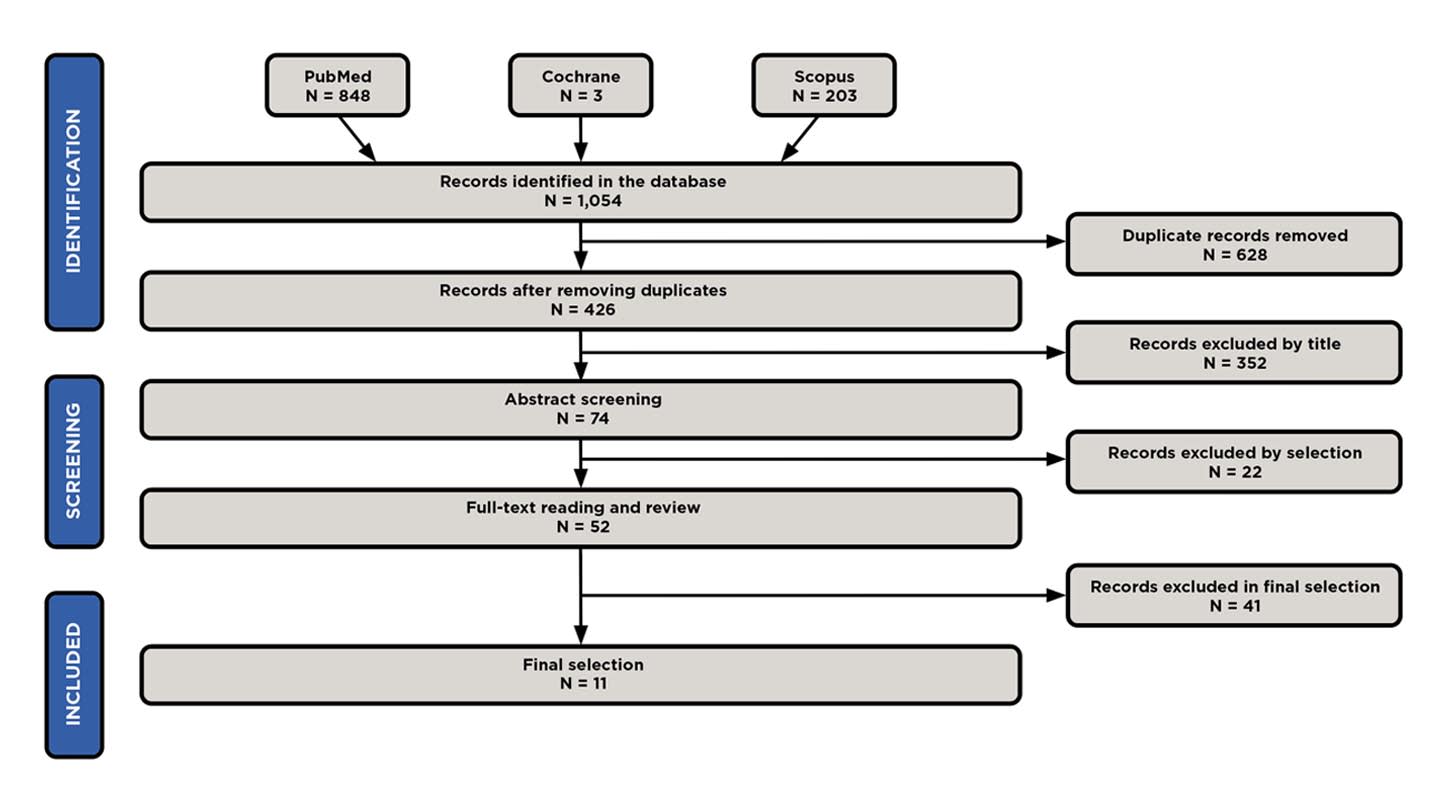

The study selection process is summarized in a PRISMA flow diagram presented in Figure 1. After conducting the initial electronic search in the various databases, the authors obtained 1,054 articles, of which 628 were duplicates. Subsequently, the authors excluded 352 articles, because they were either irrelevant to the topic, written in a language other than English or Spanish, or systematic reviews or meta-analyses. Then, 22 articles were excluded that either contained irrelevant information, did not have an available abstract, or concerned patients with facial asymmetry, cleft lip, craniofacial syndromes, or previous orthognathic surgery.

Upon reviewing the remaining 52 articles, 41 were excluded due to lack of scientific evidence, as they either were case reports or lacked conclusive findings. Therefore, the articles included in the present review amounted to 11 total, with a moderate-to-high level of evidence and a moderate-to-low risk of bias, as reflected in Table 1 and Table 2, respectively.